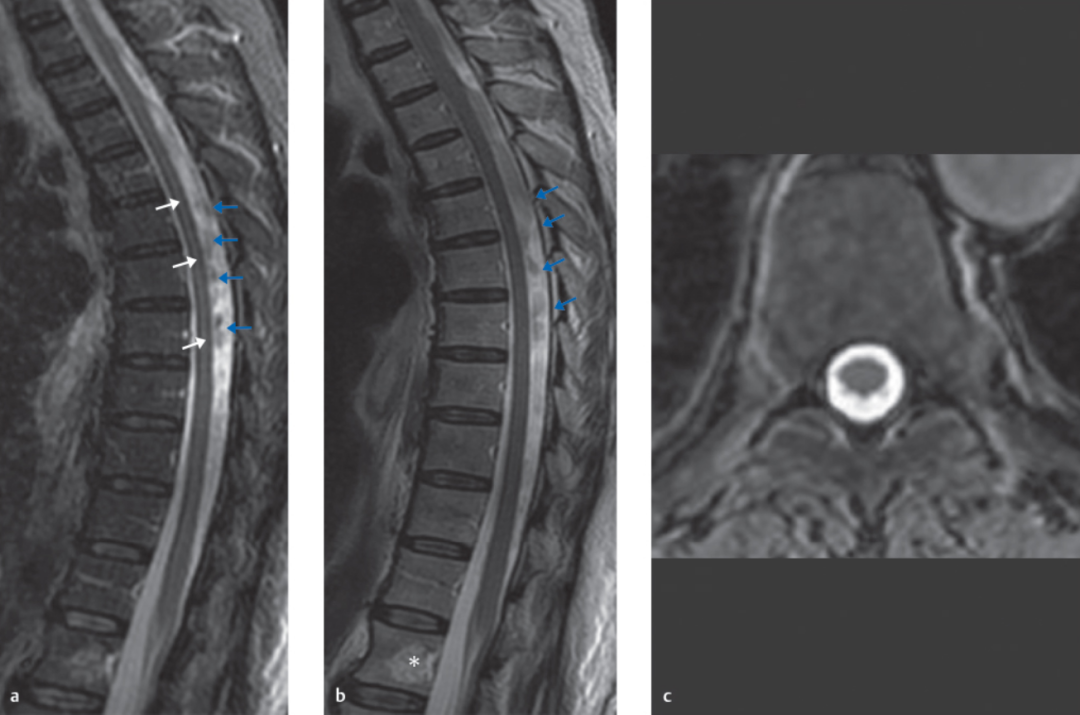

蓝色箭头所指的是由脊髓腔内脑脊液流动所形成的流动伪影,白色箭头所指的则是截断伪影。蓝色和白色箭头所呈现的征象均属于伪影,椎管和脊髓实际上是正常的,而星号区域为 L1 椎体血管瘤。